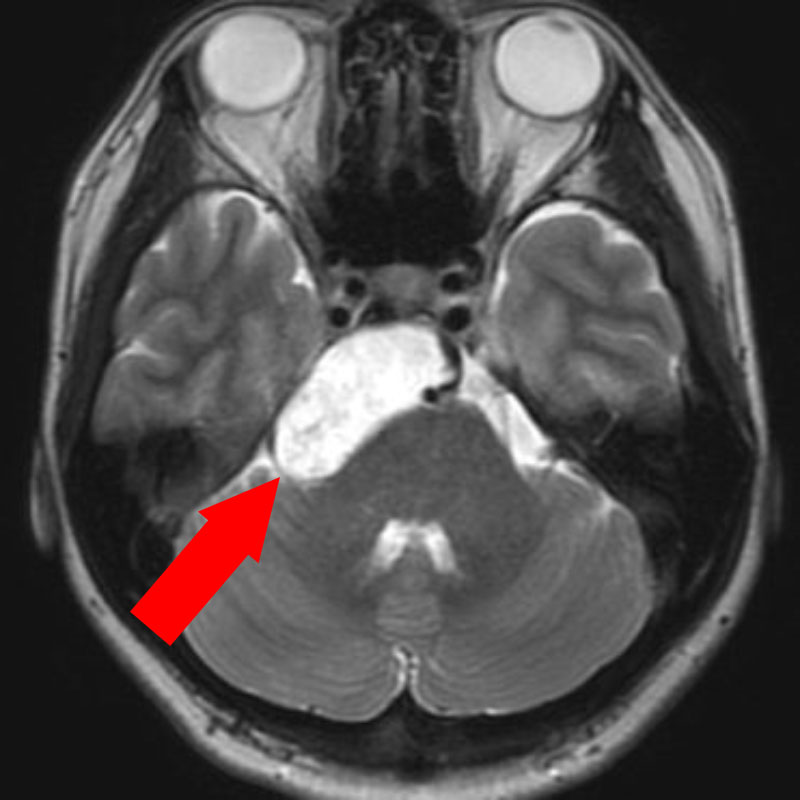

'23年7月

右小脳腫瘍

頭蓋内腫瘍摘出術

No.’23_73 手術前1

No.’23_73 手術前2